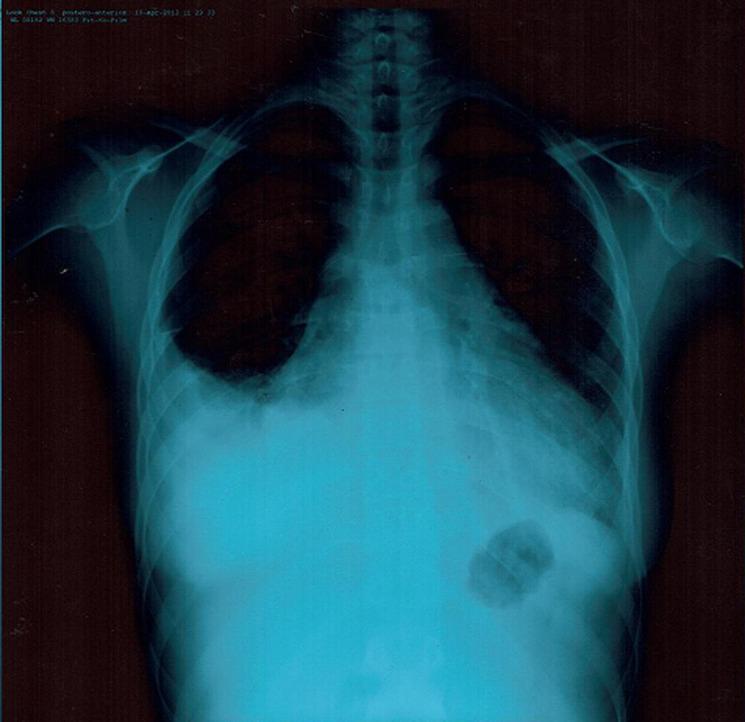

Although pericarditis is the most prevalent cardiac involvement in systemic lupus erythematosus (SLE), cardiac tamponade is extremely infrequent notably as the first manifestation of the disease. Here we report the case of a 22-year-old woman presenting with cardiac tamponade as the initial presentation of SLE.

尽管心包炎是系统性红斑狼疮(SLE)中最常见的心脏受累,但心脏压塞极为罕见,尤其是作为疾病的首发表现。在这里,我们报告了一例 22 岁女性,以心脏压塞为 SLE 的首发表现。